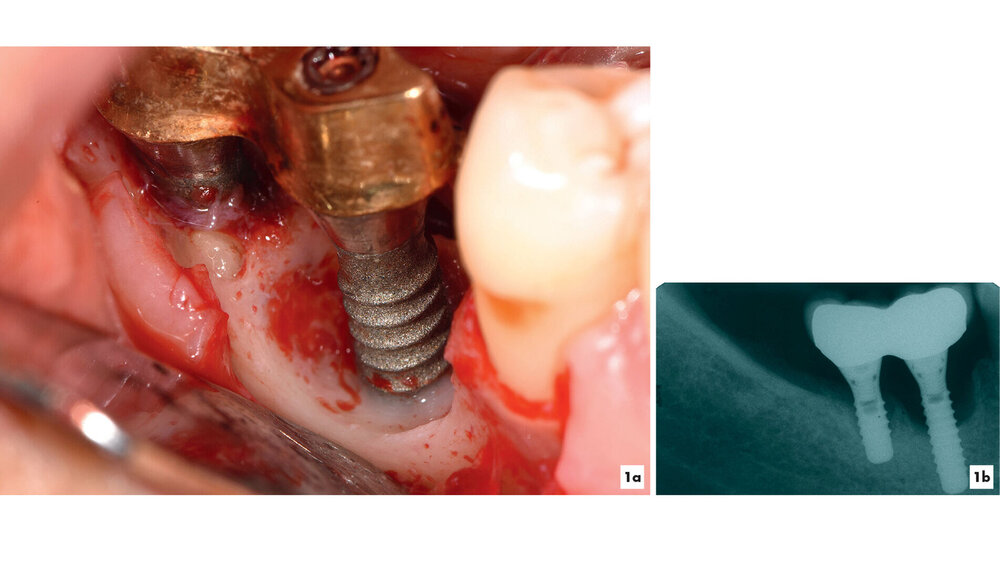

Kommt es jedoch zur Ausbildung einer Inflammation periimplantärer Gewebe ohne Knochenverlust, spricht man von einer periimplantären Mukositis. Wichtigstes Kennzeichen sind dabei die Blutung auf Sondierung und die Begrenzung der Entzündung auf das periimplantäre Saumepithel [Berglundh et al., 2018]. Breitet sich der pathologische Prozess in den Bereich des knöchernen Attachments aus, ist die Destruktion irreversibel und man spricht von einer Periimplantitis (Abbildung 1a). Zusätzlich zu den bereits genannten klinischen Kennzeichen kann man hier auch röntgenologisch den Knochenverlust feststellen, der mit erhöhten Sondierungstiefen und/oder Rezessionen einhergeht [Berglundh, 2019] (Abbildung 1b).